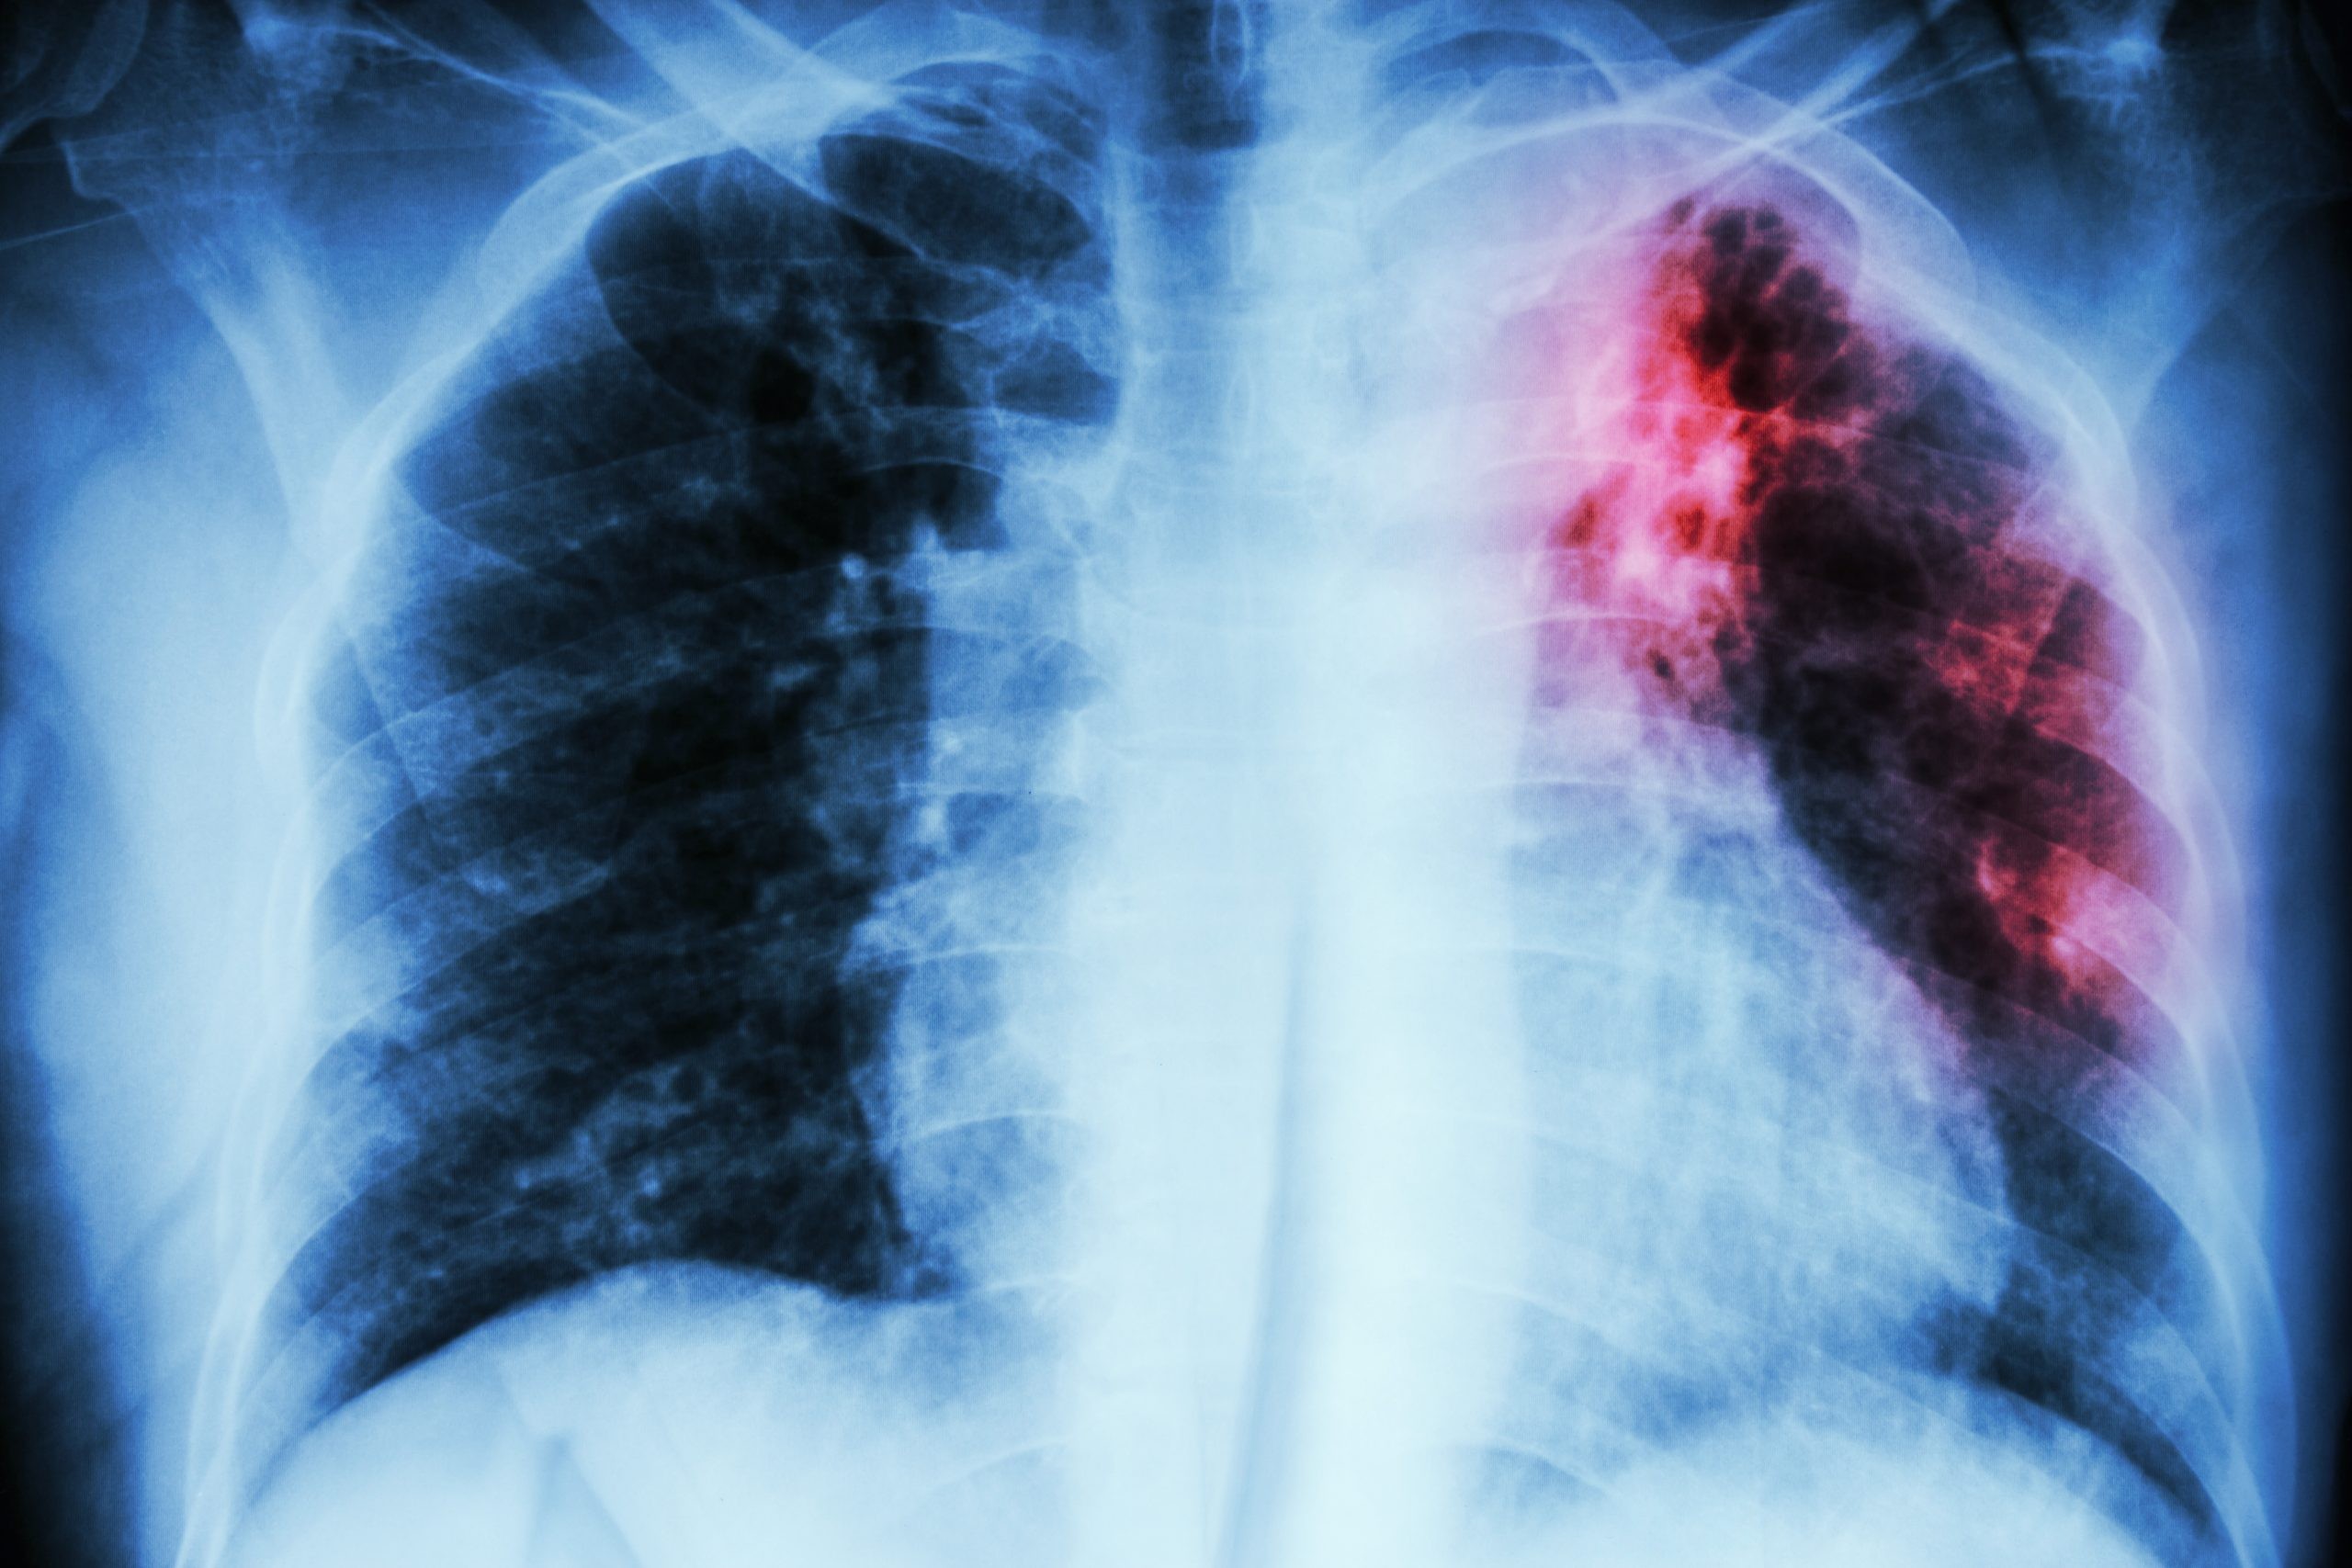

विश्व स्वास्थ्य संगठन का अनुसार सन् २०२४ मा नेपालमा मात्रै ६७ हजार नयाँ क्षयरोगी फेला परेका छन्। देशभर ६ हजार २४१ स्वास्थ्य संस्थामा उपचार सेवा उपलब्ध छ भने ७८५ संस्थामा माइक्रोस्कोपी र १४२ संस्थामा द्रुत परीक्षण सेवा निःशुल्क सञ्चालनमा छ।